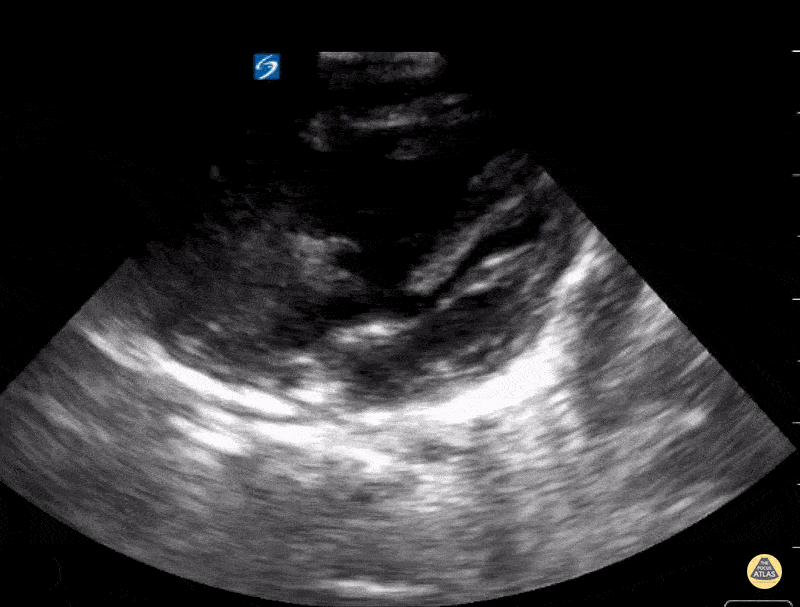

Unrepaired Tetralogy of Fallot, seen in this image is ventricular septal defect. Contributor: Kathryn Pade, MD